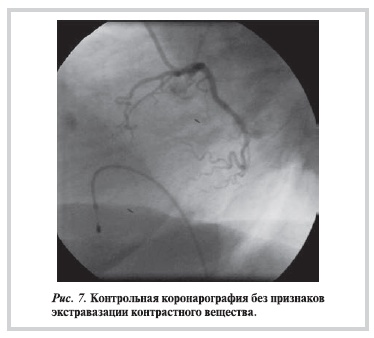

При контрольной коронарографии выявлена перфорация ПНА со сбросом контрастного вещества в перикард (рис. 6).

По проводнику на границе проксимальной и средней трети ПНА был раздут баллон 1,5×12 мм, что позволило остановить протекание контрастного вещества в перикард. На контрольной коронарограмме (рис. 7) ангиографических признаков экстравазации контрастного вещества получено не было, и больной был переведен в кардиологический блок интенсивной терапии для последующего наблюдения.